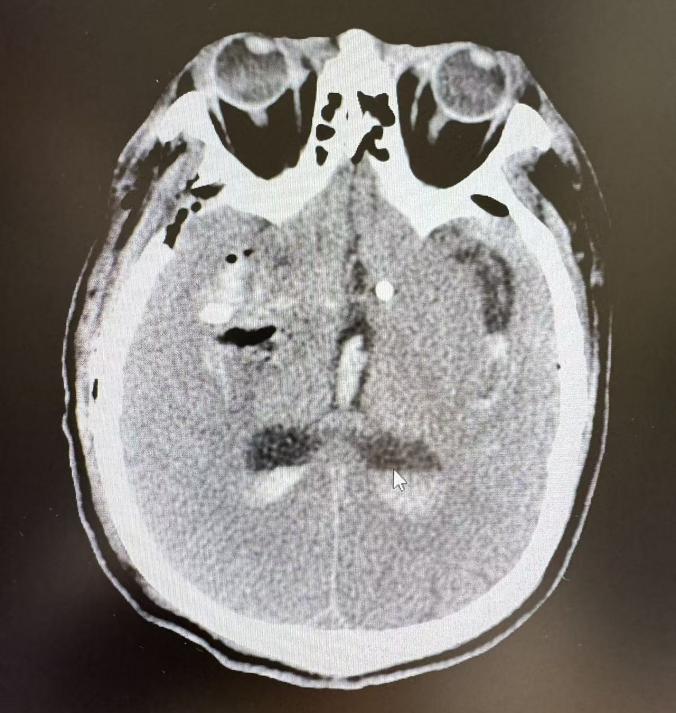

术后,复查CT显示颅内出血基本清除,脑组织受压情况明显改善。在神经外科医护人员的精心治疗和护理下,以及赵先生自身与家属的积极配合与努力,病情显著好转。患者和家属非常满意,向医护团队表达了深深的感激。

复查CT显示颅内出血基本清除